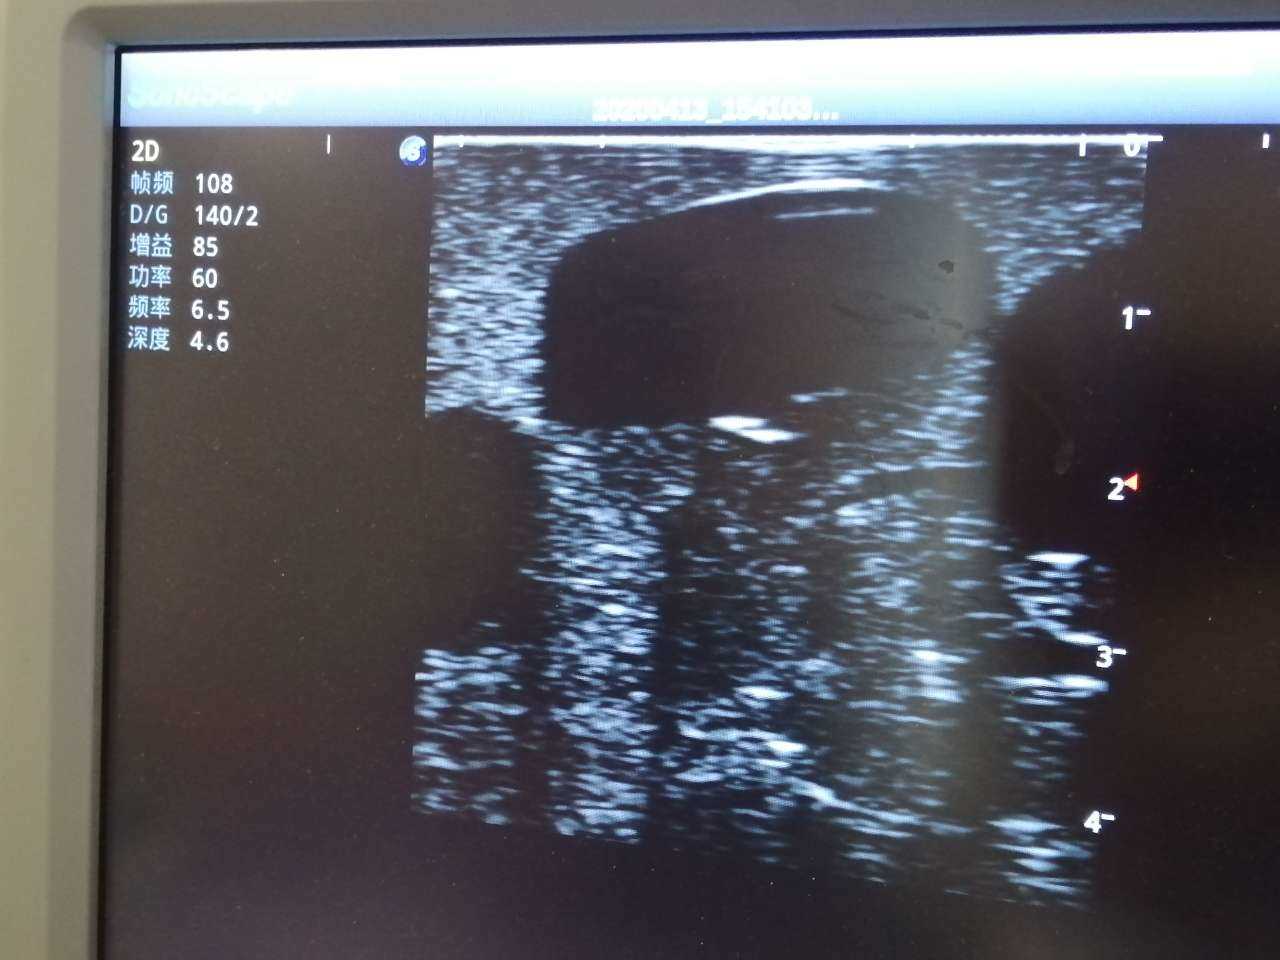

Abscess Drainage Ultrasound Trainer

Model TYE1562

The trainer is designed for abscess ultrasound recognition, drainage, surgical cutting & suturing. With realistic landmarks and high-quality images, it’s an excellent choice for abscess-related skill training and practice.

· High-quality ultrasound images to show skin, soft tissues, abscess cavity and pus